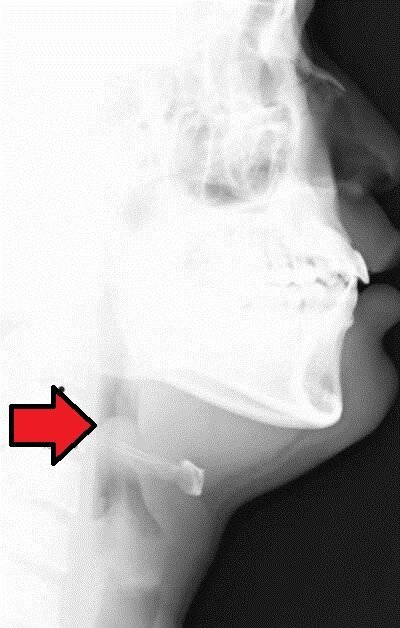

Plötzlicher Atemstillstand durch zähen Schleimpfropf in engen supraglottischen Luftwegen oder Laryngospasmus durch Untersuchung mit Mundspatel. Laryngoskopische Untersuchung nur bei Intubations- und Reanimationsbereitschaft! Laterales Röntgen: Sensitivität 88–100%.

Bei Verdacht auf Epiglottitis: Keine unnötigen Untersuchungen — zuerst den Atemweg sichern, dann diagnostizieren.